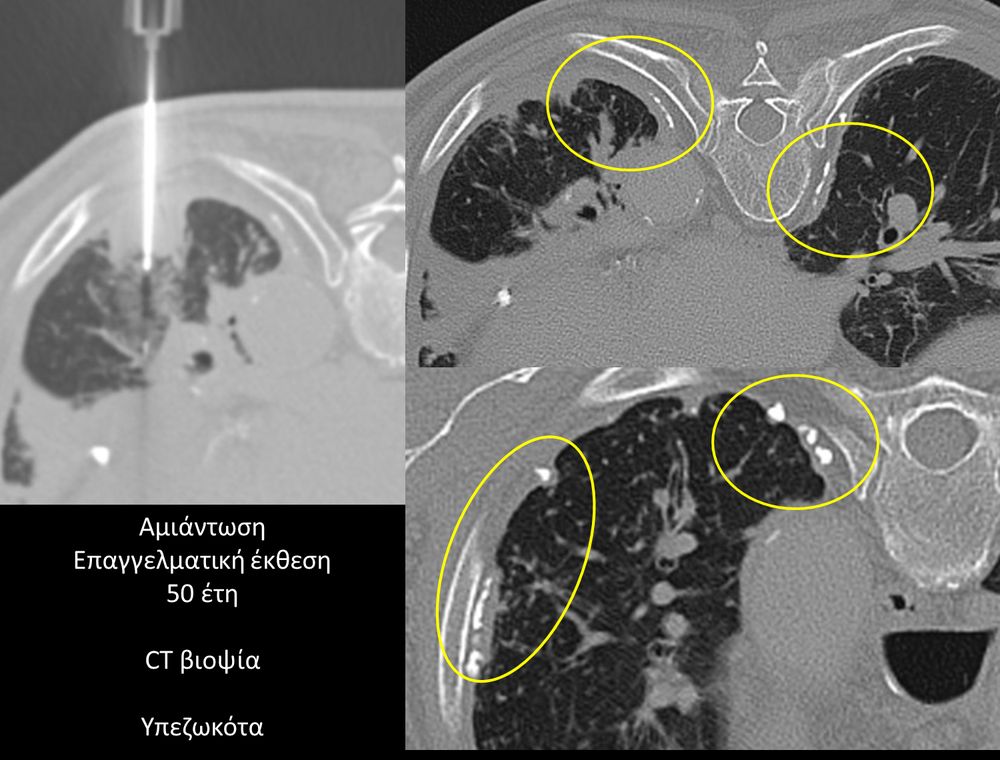

Η διαδερμική βιοψία είναι μία ελάχιστα επεμβατική μέθοδος λήψης υλικού από τον όγκο για κυτταρολογική και ιστολογική εξέταση, από εστιακές αλλοιώσεις του ήπατος, πνεύμονα, νεφρού κλπ. Συστήνεται από τον κλινικό ιατρό ανάλογα με το είδος και το μέγεθος της βλάβης και πραγματοποιείται με ασφάλεια από επεμβατικό ακτινολόγο με την καθοδήγηση αξονικού τομογράφου ή υπερήχων. Στη σύγχρονη ογκολογική θεραπεία όπου γίνεται προσπάθεια καταπολέμησης του καρκίνου σε μοριακό επίπεδο κρίνεται αναγκαία η ακριβής ιστολογική ταυτοποίηση του όγκου ώστε να εφαρμοσθεί εξατομικευμένη θεραπεία για το βέλτιστο αποτέλεσμα. Οι κατευθυνόμενες βιοψίες στοχευουν στο να παρέχουν στον κλινικό ογκολόγο το απαραίτο ιστοπαθολογικό υλικό που θα του επιτρέψει να εφαρμόσει την κατάλληλη θεραπεία για τον ογκολογικό ασθενή.